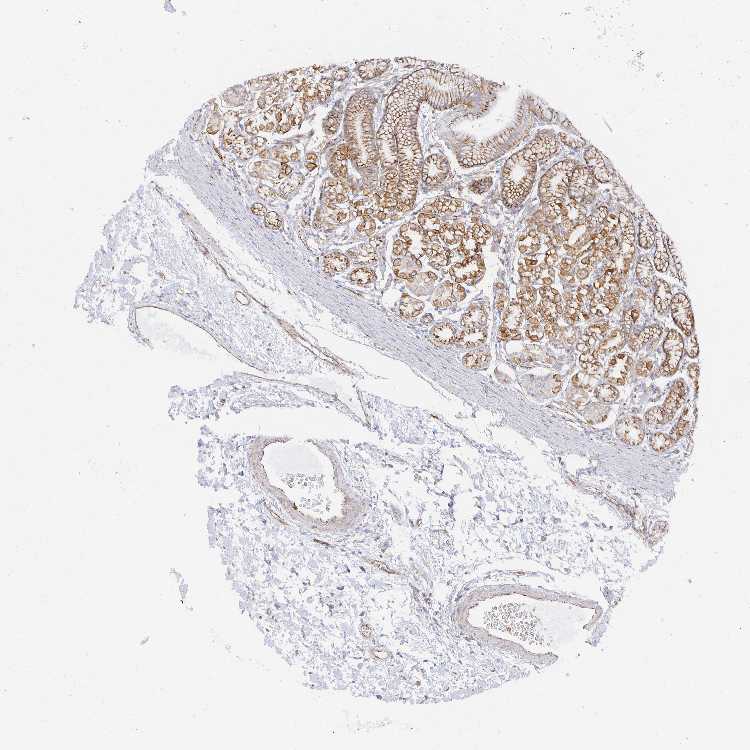

STOMACH 1 - Antibody stainingi

Antibody staining in the annotated cell types in the current human tissue is reported as not detected, low, medium, or high, based on conventional immunohistochemistry profiling in selected tissues. This score is based on the combination of the staining intensity and fraction of stained cells.

Each image is clickable and will lead to virtual microscopy that enables deeper exploration of all samples and also displays staining intensity scores, fraction scores and subcellular localization as well as patient and tissue information for each sample.

Antibody HPA055614

Glandular cells High